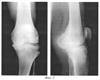

фиг.3 иллюстрирует рентгенограммы левого коленного сустава больной В., 59 лет в двух проекциях при декомпенсированной стадии остеоартроза.

Пример 3. Больная В., 59 лет (медицинская карта стационарного больного №43256). Диагноз: Левосторонний идиопатический гонартроз декомпенсированной стадии.

Клинически: определялся выраженный болевой синдром, постоянные мучительные ночные боли, нарушавшие сон и усиливающиеся к перемене погоды.

На рентгенограммах правого коленного сустава признаки остеоартроза коленного сустава: резкое сужение суставной щели в медиальном отделе сустава, заострение межмыщелковых возвышений большеберцовой кости, усиление субхондрального склероза более выраженное в медиальном отделе сустава, выраженный остеофитоз по краям суставных поверхностей (фиг.3).

С помощью предлагаемого способа диагностики произведено измерение внутрикостного давления в костно-мозговой полости левой большеберцовой кости, которое составило 28 мм рт.ст.

При сопоставлении величины внутрикостного давления с данными таблицы 1 установлено, что она соответствует декомпенсированной стадии процесса.